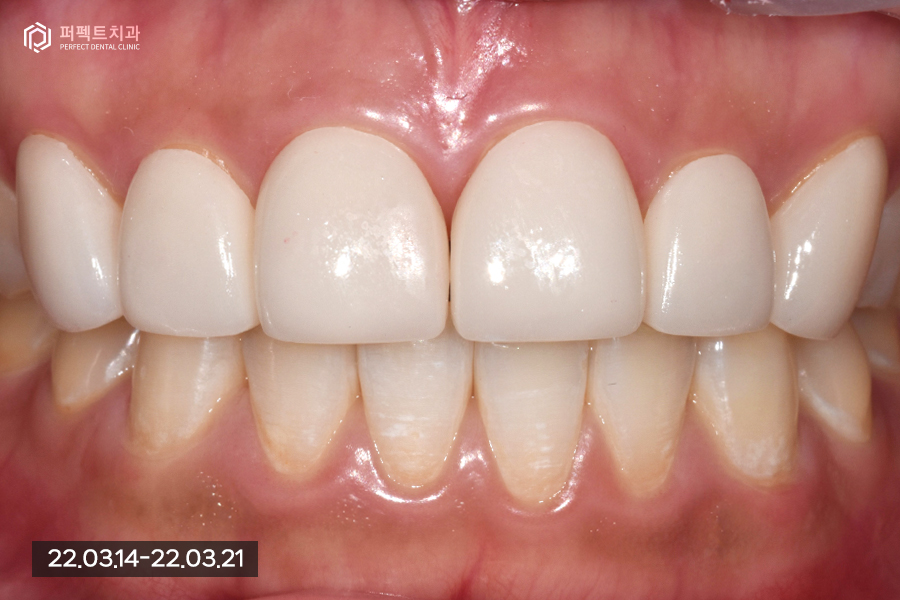

치료 후 사진을 보시면 앞니 사이 공간, 변색된 부분을 해결하였기에 환자분께서는 결과에 만족하셨지만 라미네이트 후에도 교정이 가능한지 물어보셨습니다.

라미네이트 후에도 충분히 교정치료가 가능하지만 라미네이트에 손상 없이 교정을 하기 위해 뒤로 하는 설측교정을 권해드렸고 교정을 고민해보신다고 하셨습니다 :)

오늘은 세가지 문제가 있는 폴리네이트 케이스를 확인해봤는데요. 환자분께서는 결과에 만족을 하셨고 후에도 돌출에 대한 문제 해결 대안이 있었기 때문에 이에 대해 고민을 해보신다고 하셨습니다.